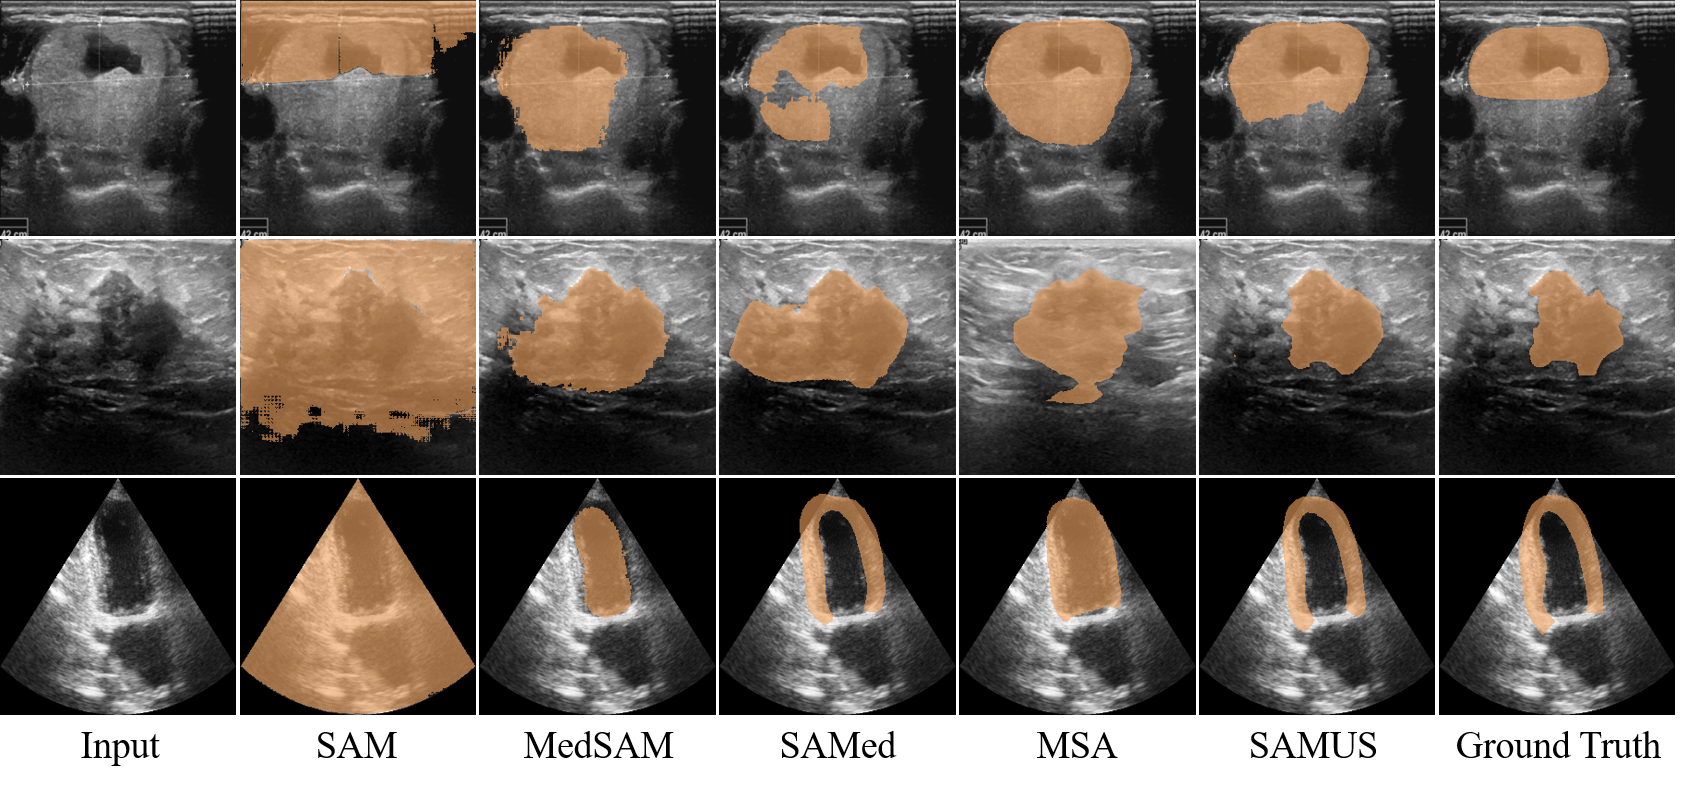

Qualitative results: Qualitative segmentation results of different foundation models, including SAM, MedSAM, SAMed, MSA, and SAMUS, are presented in Fig. 5. Without tuning in medical images, SAM completely loses the ability to segment everything. Through applying tuning methods to SAM, MedSAM, SAMed, and MSA can somewhat restore the segmentation capability of SAM. However, they still struggle to accurately delineate segmentation boundaries in ultrasound images, resulting in extensive false negatives and false positives. In contrast, SAMUS exhibits superior performance by accurately locating segmentation boundaries, even for the low-contrast ones. It is consistent with the analysis that complementing local information with the image encoder is helpful, especially for boundary/shape preservation in medical image segmentation.